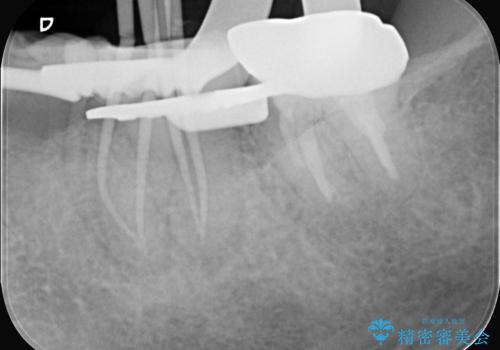

- 治療計画

- 患者様は、右側の奥歯でしっかり噛めないことを主訴に来院されました。診察の結果、右上6・右下6の根管治療が不十分で、感染のリスクがある状態と判断。これらの歯は再根管治療を行い、セラミッククラウンで補綴することにしました。また、右上7・右下7は欠損しており、噛み合わせを回復するためにインプラント治療を計画しました。

まず、右上6・右下6の根管治療を再度行い、根の状態をしっかり整えた上で、セラミッククラウンを装着しました。さらに、欠損していた右上7・右下7にはインプラントを埋入し、セラミッククラウンを装着。治療後は、「奥歯でしっかり噛めるようになり、不安なく食事ができるようになった」と患者様にも大変ご満足いただきました。